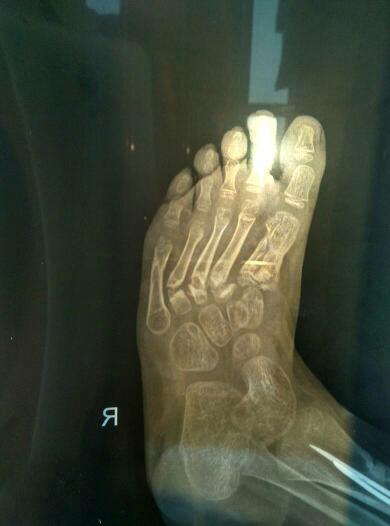

四岁小孩因为车祸导致右脚跖骨1-5粉碎性骨折,目前已经七个月,小拇指跟大拇指差不多长好了2-4三个 四岁小孩因为车祸导致右脚跖骨1-5粉碎性骨折,目前已经七个月,小拇指跟大拇指差不多长好了2_4三个脚趾恢复不乐观,靠近骨骺这个地方明显往做歪,骨头也没有对齐,医生说骨骺伤的厉害怕骨头不长, 点击展开 匿名用户 2016-03-28 18:08 满意回答 建议外敷专门针对骨折康复的膏药,可以接骨续筋促进骨头愈合 匿名用户 2016-03-29 09:03 宝宝知道提示您:回答为网友贡献,仅供参考。 相关问题 右脚234跖骨粉碎性骨折,钢板固定手术2月,现 三岁宝宝被压面机压断大拇指小拇指!以后能接好吗? 脚的小拇指比和大拇指一样长,这是为何?